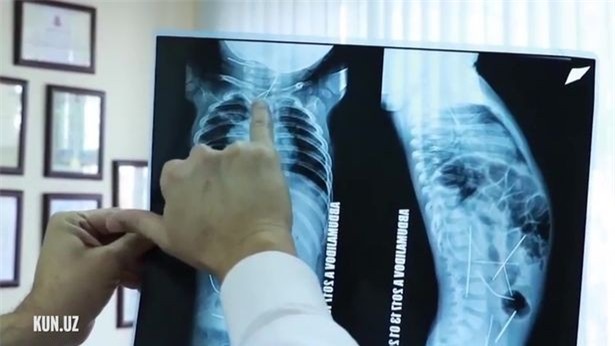

Các bác sĩ ở Uzbekistan vừa phẫu thuật rút 16 cây kim trong người một đứa trẻ 11 tháng tuổi sau khi mẹ của bé đưa đến bệnh viện vì sốt cao và khó khăn khi đi vệ sinh. Ban đầu, các bác sĩ và y tá cho rằng em bé bị viêm phổi, nhưng hình chụp X-quang cho thấy có rất nhiều cây kim nằm trong tim, bàng quang, đại tràng, cột sống và cổ.

Hình chụp X-quang cho thấy có rất nhiều cây kim nằm trong tim, bàng quang, đại tràng, cột sống và cổ của đứa trẻ. (Ảnh: Internet)